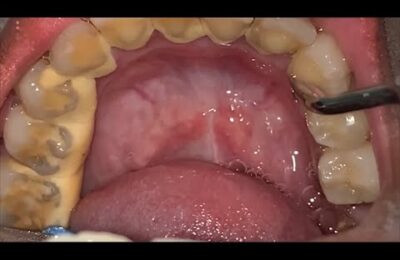

Dentist Looking Tooth Cavity #dentist #satisfying

Dentist Looking Tooth Cavity #dentist #satisfying #shorts.